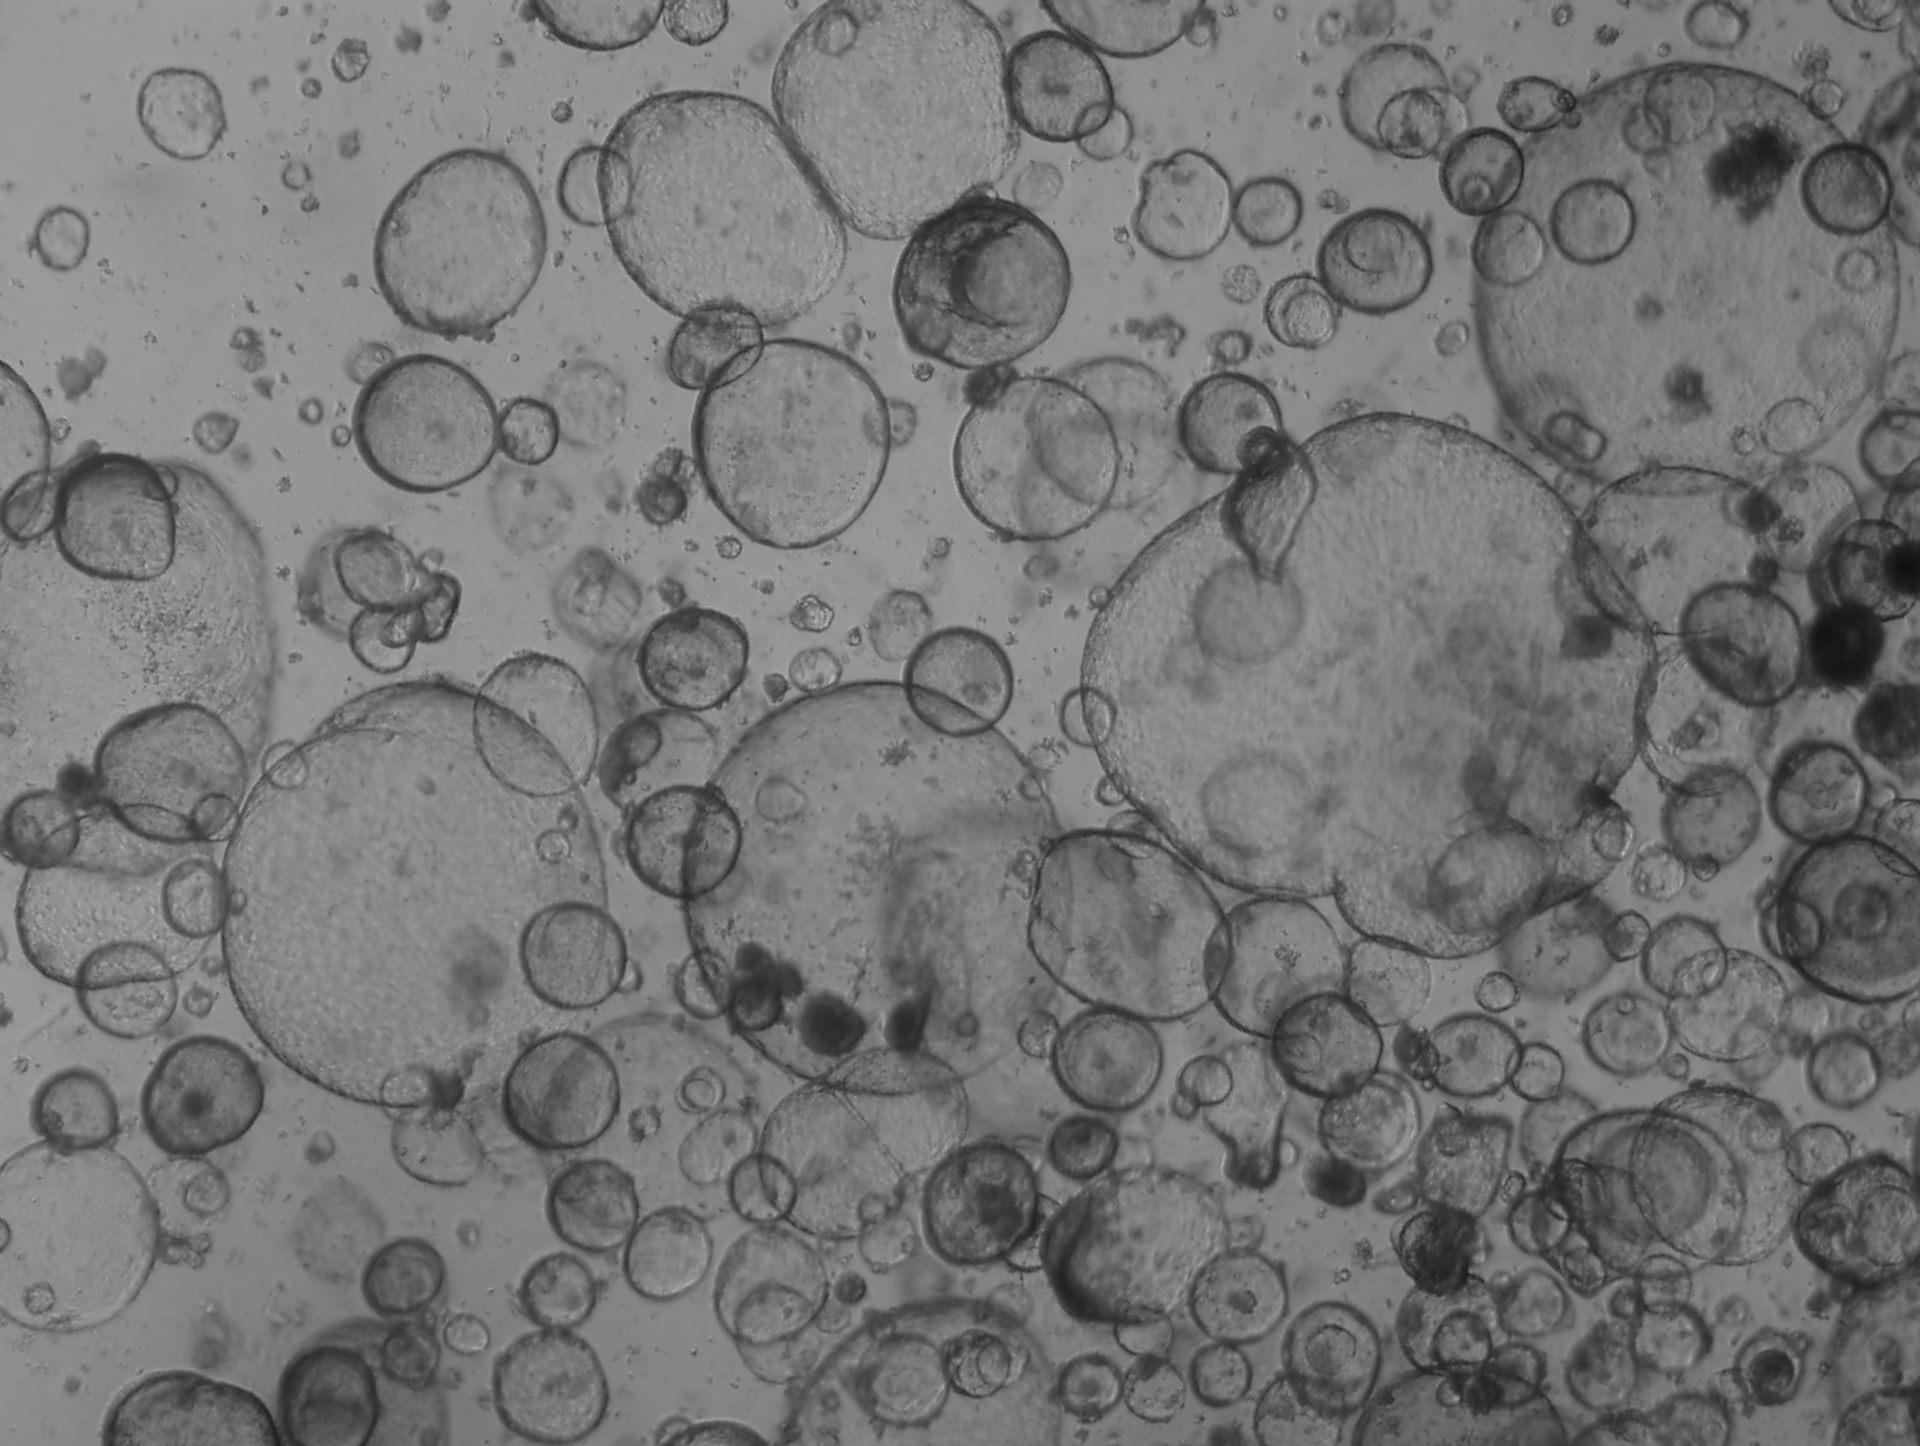

Células ductales pancreáticas de ratón. (Habib Rezanejad)

En mi propia investigación, mi laboratorio cultiva organoides a partir de tejido pancreático humano y de ratón para estudiar la diversidad celular y la inflamación del páncreas. Estos modelos nos permiten investigar cómo se comportan los diferentes tipos de células pancreáticas en tres dimensiones, algo que sería imposible de observar en los cultivos tradicionales de células planas.